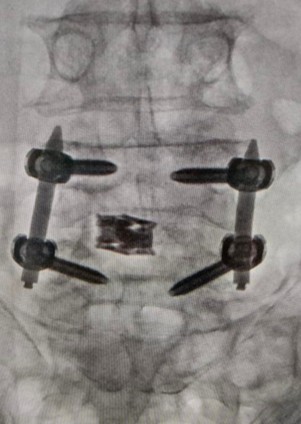

Our team treats patients who need repair of spinal deformities due to scoliosis, kyphosis, spondylolisthesis, infection, tumors, and trauma — following international standards of care.

While proud of our surgical success, we also take pride in treating patients without surgery. Nearly 80–90% of cases are managed conservatively with medicines, physiotherapy, and pain procedures for faster recovery.